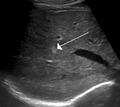

Capillary hemangioma

The majority of IHs can be diagnosed by history and physical examination.[20] In rare cases, imaging (ultrasound with Doppler, magnetic resonance imaging), and/or cytology or histopathology are needed to confirm the diagnosis.[21][22] IHs are usually absent at birth or a small area of pallor, telangiectasias, or duskiness may be seen. A fully formed mass at birth usually indicates a diagnosis other than IH. Superficial hemangiomas in the upper dermis have a bright-red strawberry color, whereas those in the deep dermis and subcutis, deep hemangiomas, may appear blue and be firm or rubbery on palpation. Mixed hemangiomas can have both features.[20] A minimally proliferative IH is an uncommon type that presents with fine macular telangiectasias with an occasional bright-red, papular, proliferative component. Minimally proliferative IHs are more common in the lower body.[23]

A precise history of the growth characteristics of the IH can be very helpful in making the diagnosis. In the first 4 to 8 weeks of life, IHs grow rapidly with primarily volumetric rather than radial growth. This is usually followed by a period of slower growth that can last 6–9 months, with 80% of the growth completed by 3 months. Finally, IHs involute over a period of years.[24] The exceptions to these growth characteristics include minimally proliferative His, which do not substantially proliferate[23] and large, deep IHs in which noticeable growth starts later and lasts longer.[24] If the diagnosis is not clear based on physical examination and growth history (most often in deep hemangiomas with little cutaneous involvement), then either imaging or histopathology can help confirm the diagnosis.[21][25] On Doppler ultrasound, an IH in the proliferative phase appears as a high-flow, soft-tissue mass usually without direct arteriovenous shunting. On MRI, IHs show a well-circumscribed lesion with intermediate and increased signal intensity on T1- and T2-weighted sequences, respectively, and strong enhancement after gadolinium injections, with fast-flow vessels.[21] Tissue for diagnosis can be obtained via fine-needle aspiration, skin biopsy, or excisional biopsy.[26] Under the microscope, IHs are unencapsulated aggregates of closely packed, thin-walled capillaries, usually with endothelial lining. Blood-filled vessels are separated by scant connective tissue. Their lumina may be thrombosed and organized. Hemosiderin pigment deposition due to vessel rupture may be observed.[27] The GLUT-1 histochemical marker can be helpful in distinguishing IHs from other items on the differential diagnosis, such as vascular malformations.[22]